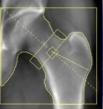

Osteodensitometrie mit Dexa-Methode - Osteologie (n. DVO)

Wir betrachtens es als eine unserer ärzlichen Aufgaben, Erkrankungen des Knochens möglichst früh zu erkennen und zu behandeln. Dabei orientieren wir uns an den Leitlinien der Dachgesellschaft für Osteologie (DVO) und deren Qualitätskriterien. Die Knochendichtemessung mittels der DEXA-Methode ist eine technische Standarduntersuchung zur Erkennung von Knochenmineralverlusten. Wir bieten diese Untersuchung in unserer Praxis an.